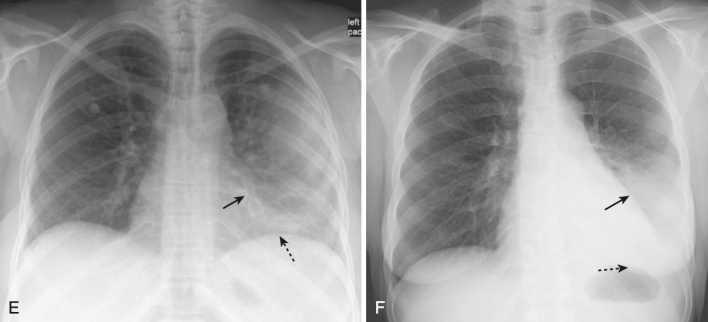

- Điển hình biểu hiện là một viêm phổi kẽ dạng lưới, quanh rốn phổi hoặc như một bệnh khoảng chứa khí có thể trông giống như dạng phân bố trung tâm của phù phổi (Hình 5).

- Các biểu hiện khác, chẳng hạn như bệnh khoảng chứa khí một bên hoặc bệnh khoảng chứa khí loang lổ ít phổ biến hơn.

- Thường không có tràn dịch màng phổi và không có hạch rốn phổi